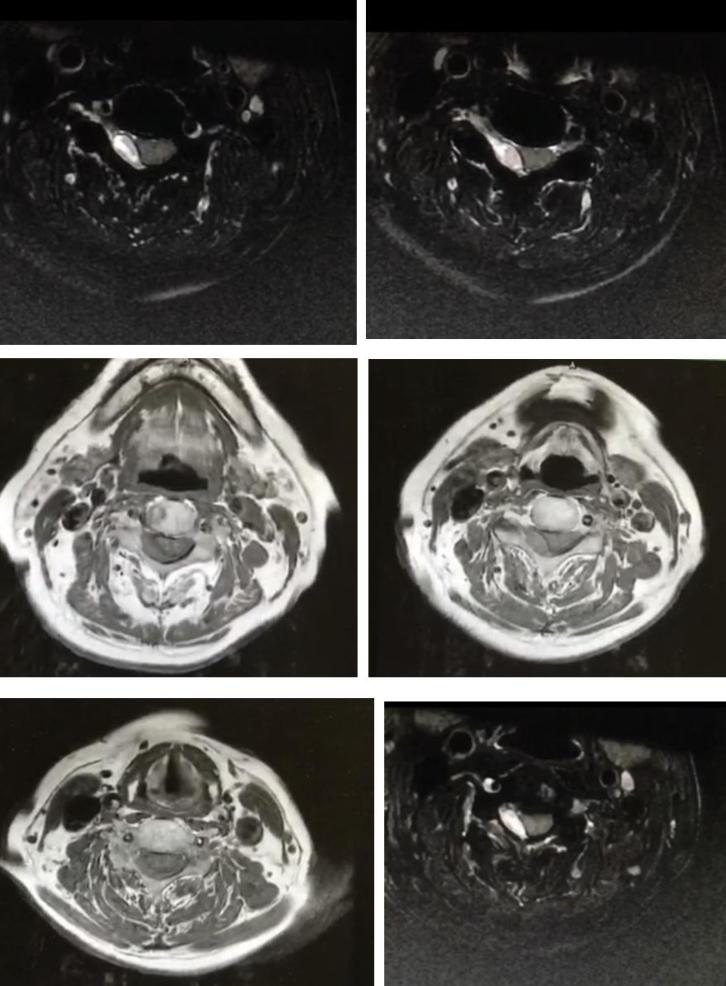

男性68岁,四肢末梢麻木2月余,伴有站立不稳,加重1周,不能独立行走。查体双侧跟膝胫试验欠稳准,双侧位置觉、震动觉减退。

答案:脊髓亚急性联合变性。患者老年男性,亚急性病程,以深感觉受累为主要表现,脊髓影像长节段病灶,轴位显示后索病灶“圆点征”,颅内影像改变无特异性,NMOSD相关抗体检测以及OB均阴性。其特征性影像有“圆点征”、“小字征”、“三角征”、“八字征”等。